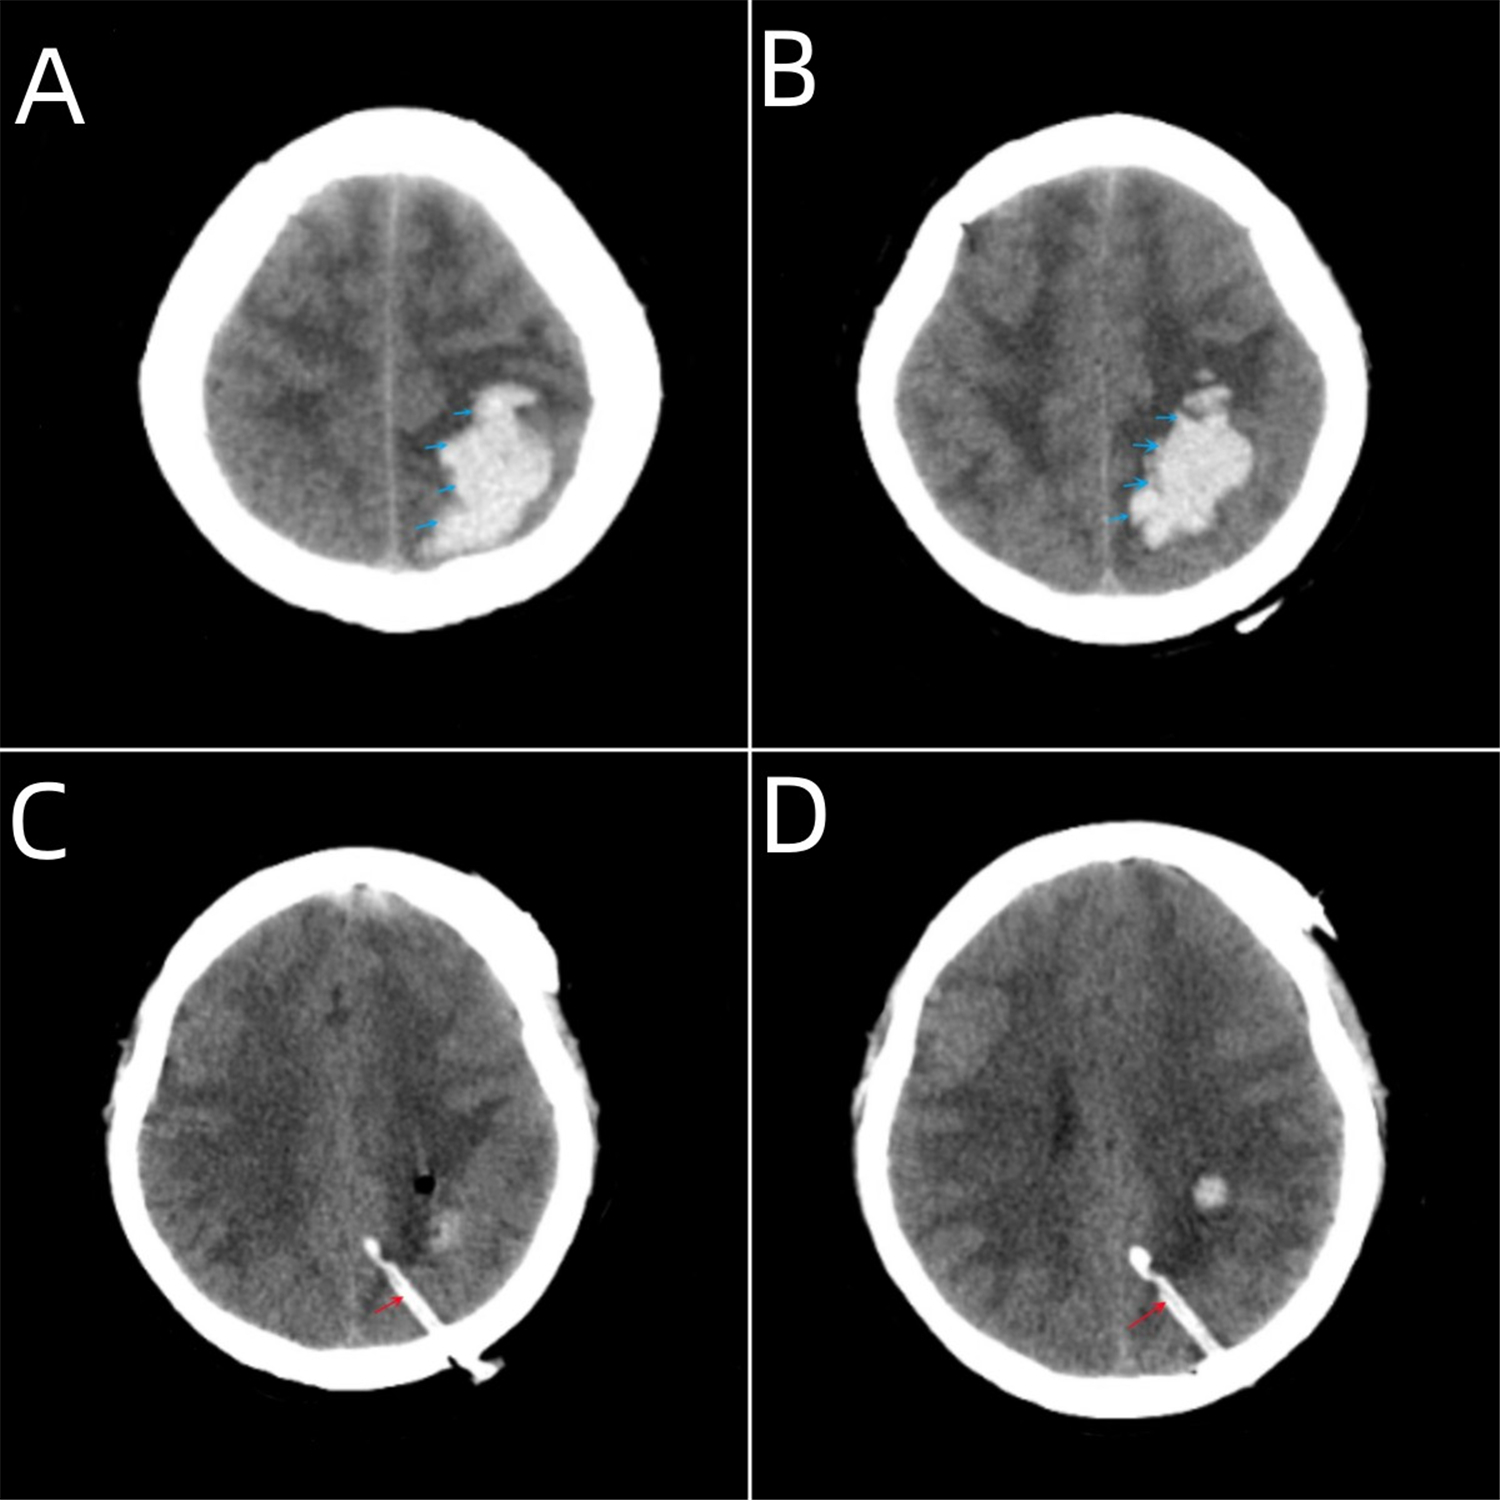

图A、B为术前颅脑CT,可见顶枕叶脑出血,蓝色箭头所示为出血部位。

图C、D为术后复查颅脑CT,可见颅内血肿清除效果良好,无二次出血,红色箭头所指为引流管所在位置。